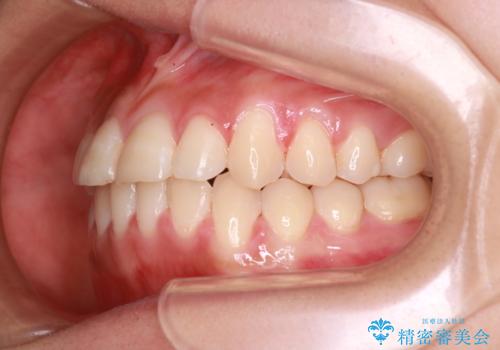

- 前歯のガタガタを主訴に来院されました。

装着時間に不安がある人は、ワイヤー矯正をおすすめしております。短期間で治療でき患者様にも満足していただきました。